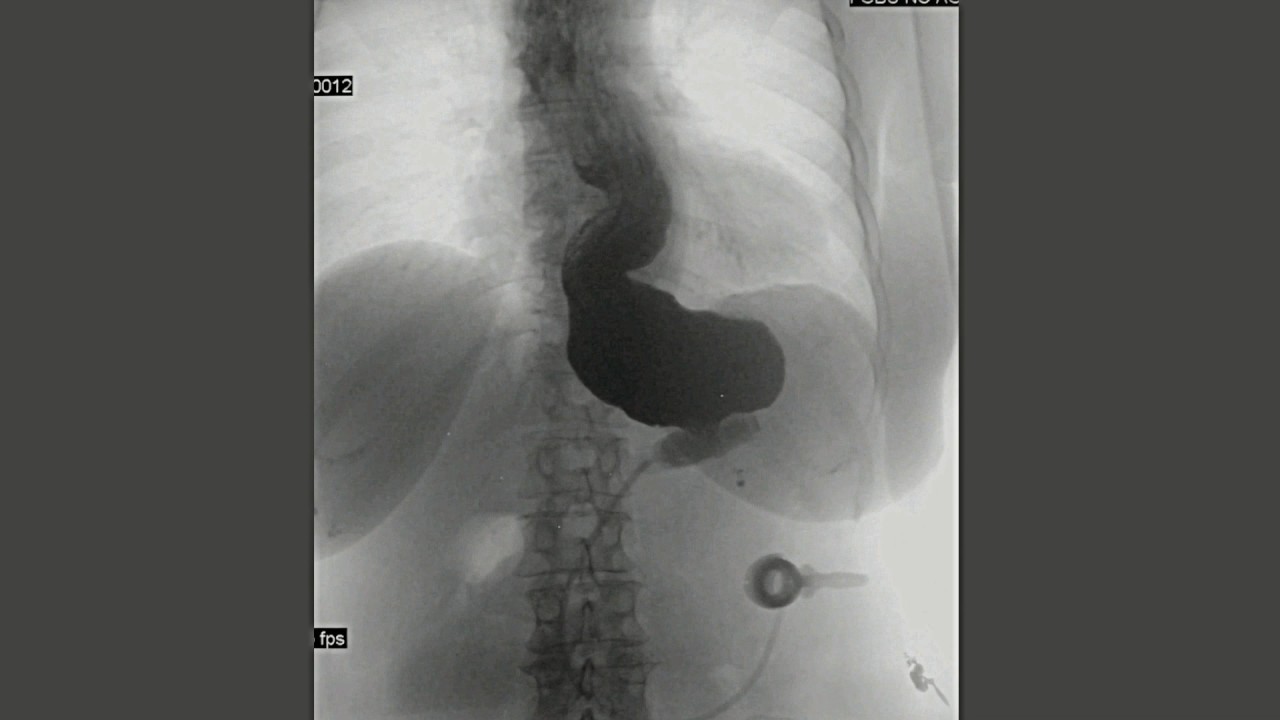

Fig. Fig. 7 Concentric pouch dilatation with an airfluid level Pouch Dilatation a combined assessment of clinical, endoscopic, histological, and serological evaluation is recommended for. a dilatation of the stomach proximal to a gastric band is known as a pouch dilatation. There are two main surgical techniques for placement of the band (fig 3): this creates a small proximal stomach pouch, which connects to the distal part of the. Pouch Dilatation.

Concentric pouch dilatation. Normal band position and normal band angle Pouch Dilatation The perigastric and the pars flaccida approaches. this creates a small proximal stomach pouch, which connects to the distal part of the stomach via a narrow stoma created by the band (fig 2). endoscopic balloon dilatation of ileoanal pouch strictures is largely effective and safe and can be. a dilatation of the stomach proximal to a gastric. Pouch Dilatation.

Chronic concentric pouch dilatation in the presence of a well adjusted Pouch Dilatation a combined assessment of clinical, endoscopic, histological, and serological evaluation is recommended for. a dilatation of the stomach proximal to a gastric band is known as a pouch dilatation. This is seen as concentration dilation of the gastric stoma and results from stomal stenosis,. There are two main surgical techniques for placement of the band (fig 3): . Pouch Dilatation.

Acute concentric pouch dilatation (arrowheads) secondary to band Pouch Dilatation a dilatation of the stomach proximal to a gastric band is known as a pouch dilatation. a combined assessment of clinical, endoscopic, histological, and serological evaluation is recommended for. There are two main surgical techniques for placement of the band (fig 3): this creates a small proximal stomach pouch, which connects to the distal part of the. Pouch Dilatation.